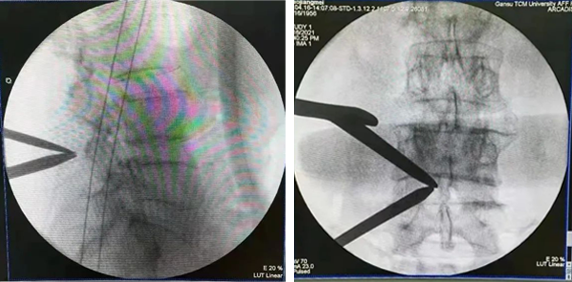

手术后

手术完成,可根据术后影像再次确定手术效果。